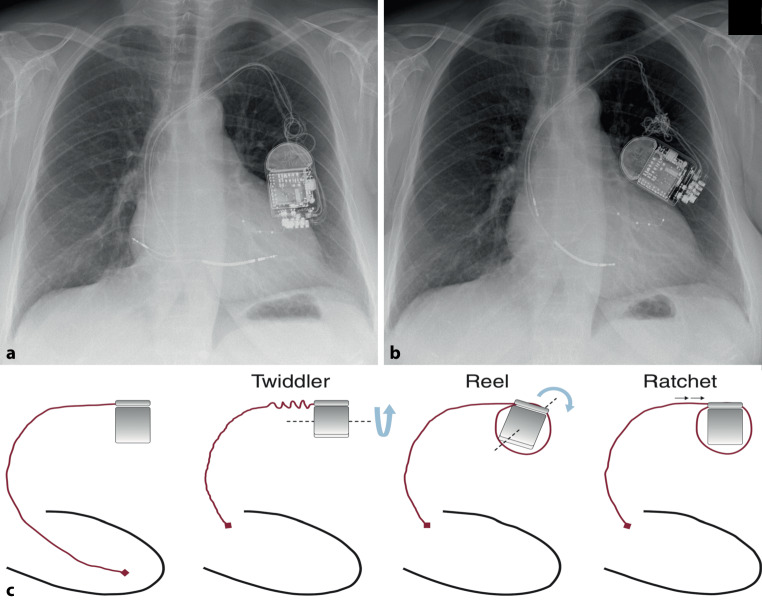

扭转:ct - d表现为Twiddler和Reel混合证。

Twists and turns: CRT-D with mixed Twiddler and Reel syndromes.